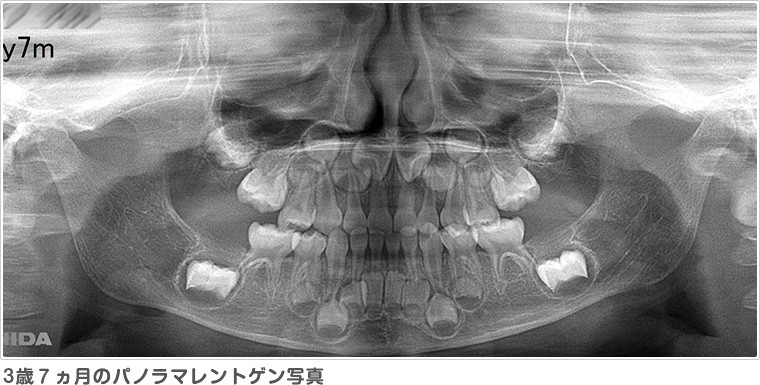

レントゲンは通常大きなレントゲンを2枚撮影します。パノラマレントゲンからは、おもに将来の永久歯の数が足りているか、永久歯の前歯はどのような形で生えてくるか、スペース不足はどのくらいか、などを予測します。セファロレントゲンからは、顔に対してアゴや歯並びがどのくらいの位置にあるのか、将来どのように成長する傾向があるのか、などを基準となる位置の角度を測って計測します。